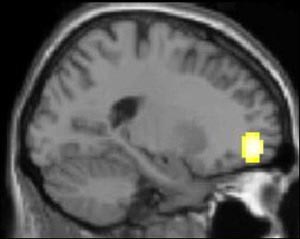

In

an experiment using functional magnetic resonance imaging

(fMRI), a group of healthy people and a group of depressed

people were shown clips from sad films. Both groups were

asked to try to suppress any feelings of sadness that the

films elicited.

The image here represents the arithmetical difference between

the brain activity levels of healthy subjects and of depressed

subjects. It shows that the healthy subjects had more activity

in the lateral portion of the orbitofrontal cortex (Brodmann

area 11), which plays a major role in regulating emotions.

This is not surprising: since depressed people have a lot of

trouble in inhibiting their negative emotions, it makes sense

that their orbitofrontal cortexes would be less active than

those of healthy people.

Source: Mario Beauregard, Centre

de recherche de l'Institut universitaire de gériatrie

de Montréal |